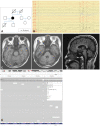

A Novel KCNA1 Mutation in an Episodic Ataxia Type 1 Patient with Asterixis and Falls